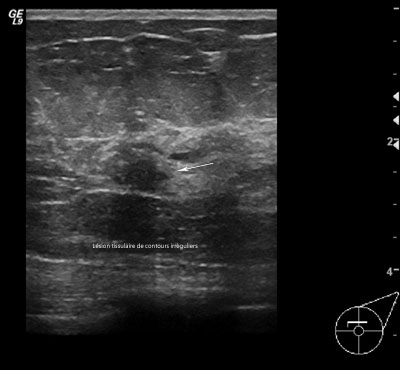

Masse ACR5 de contours irréguliers

- ACR 5 : L'anomalie est évocatrice d'un cancer.